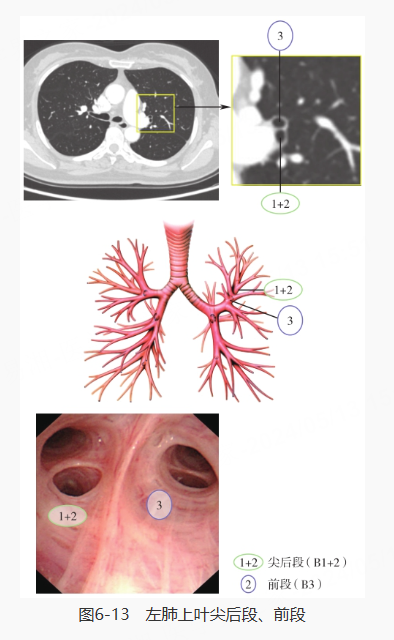

再对左肺进行探查,分别是左主支气管、左肺上叶·下叶、左肺上叶上支·舌支、左肺上叶尖后段·前段、左肺上叶上舌段·下舌段、左肺下叶、左肺下叶背段、左肺下叶基底段: